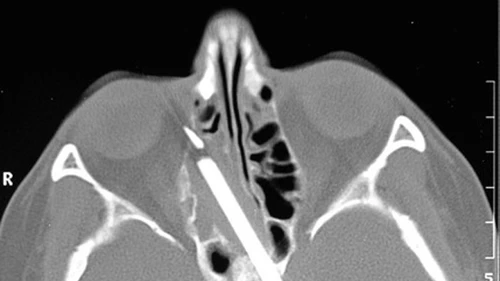

Con una tomografía detectaron un lápiz de 10 centímetros (4 pulgadas) alojado entre el seno nasal y la faringe, y que había causado una lesión en la órbita del ojo derecho.